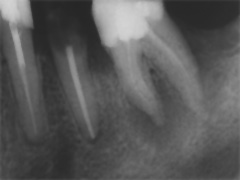

Aufbissempfindlichkeit an 33 veranlasste uns erstmalig in dieser Kieferregion zu röntgen. Mit grossen Augen sahen wir dann an, was uns auch ansah. Einen Knochendefekt dieser Grössenordnung mit seiner schaurigen Aura sieht man zum Glück nicht jeden Tag. Doch, obgleich das Alien dereinst Zahn 34 entsprang, war eine Behandlung nur am Zahn davor durchsetzbar. Dessen Wurzelfüllung erfolgte regulär nach 14 Tagen, neue Terminangebote aber wurden, weil angeblich nicht mehr nötig, verschmäht.

Keine 8 Wochen gingen noch in's Land, bis das mit Macht geschah, was lange schon erwartet war. Das Arbeitsprogramm bestand aus Eröffnung von Zahn 34 und einer Schwellung inkl. Drainage, am nächsten Tag dann noch Aufbereitung des Kanals mit Einlage. 2 Wochen später dann die Füllung plus einem als Resektion deklarierten Auslöffeln des Granu­lationsgewebes durch eine Mini-Öffnung, zu deren Verschluss eine Naht genügte.

3 Aufnahmen sind von 2001, die vierte vom Nov. 2006